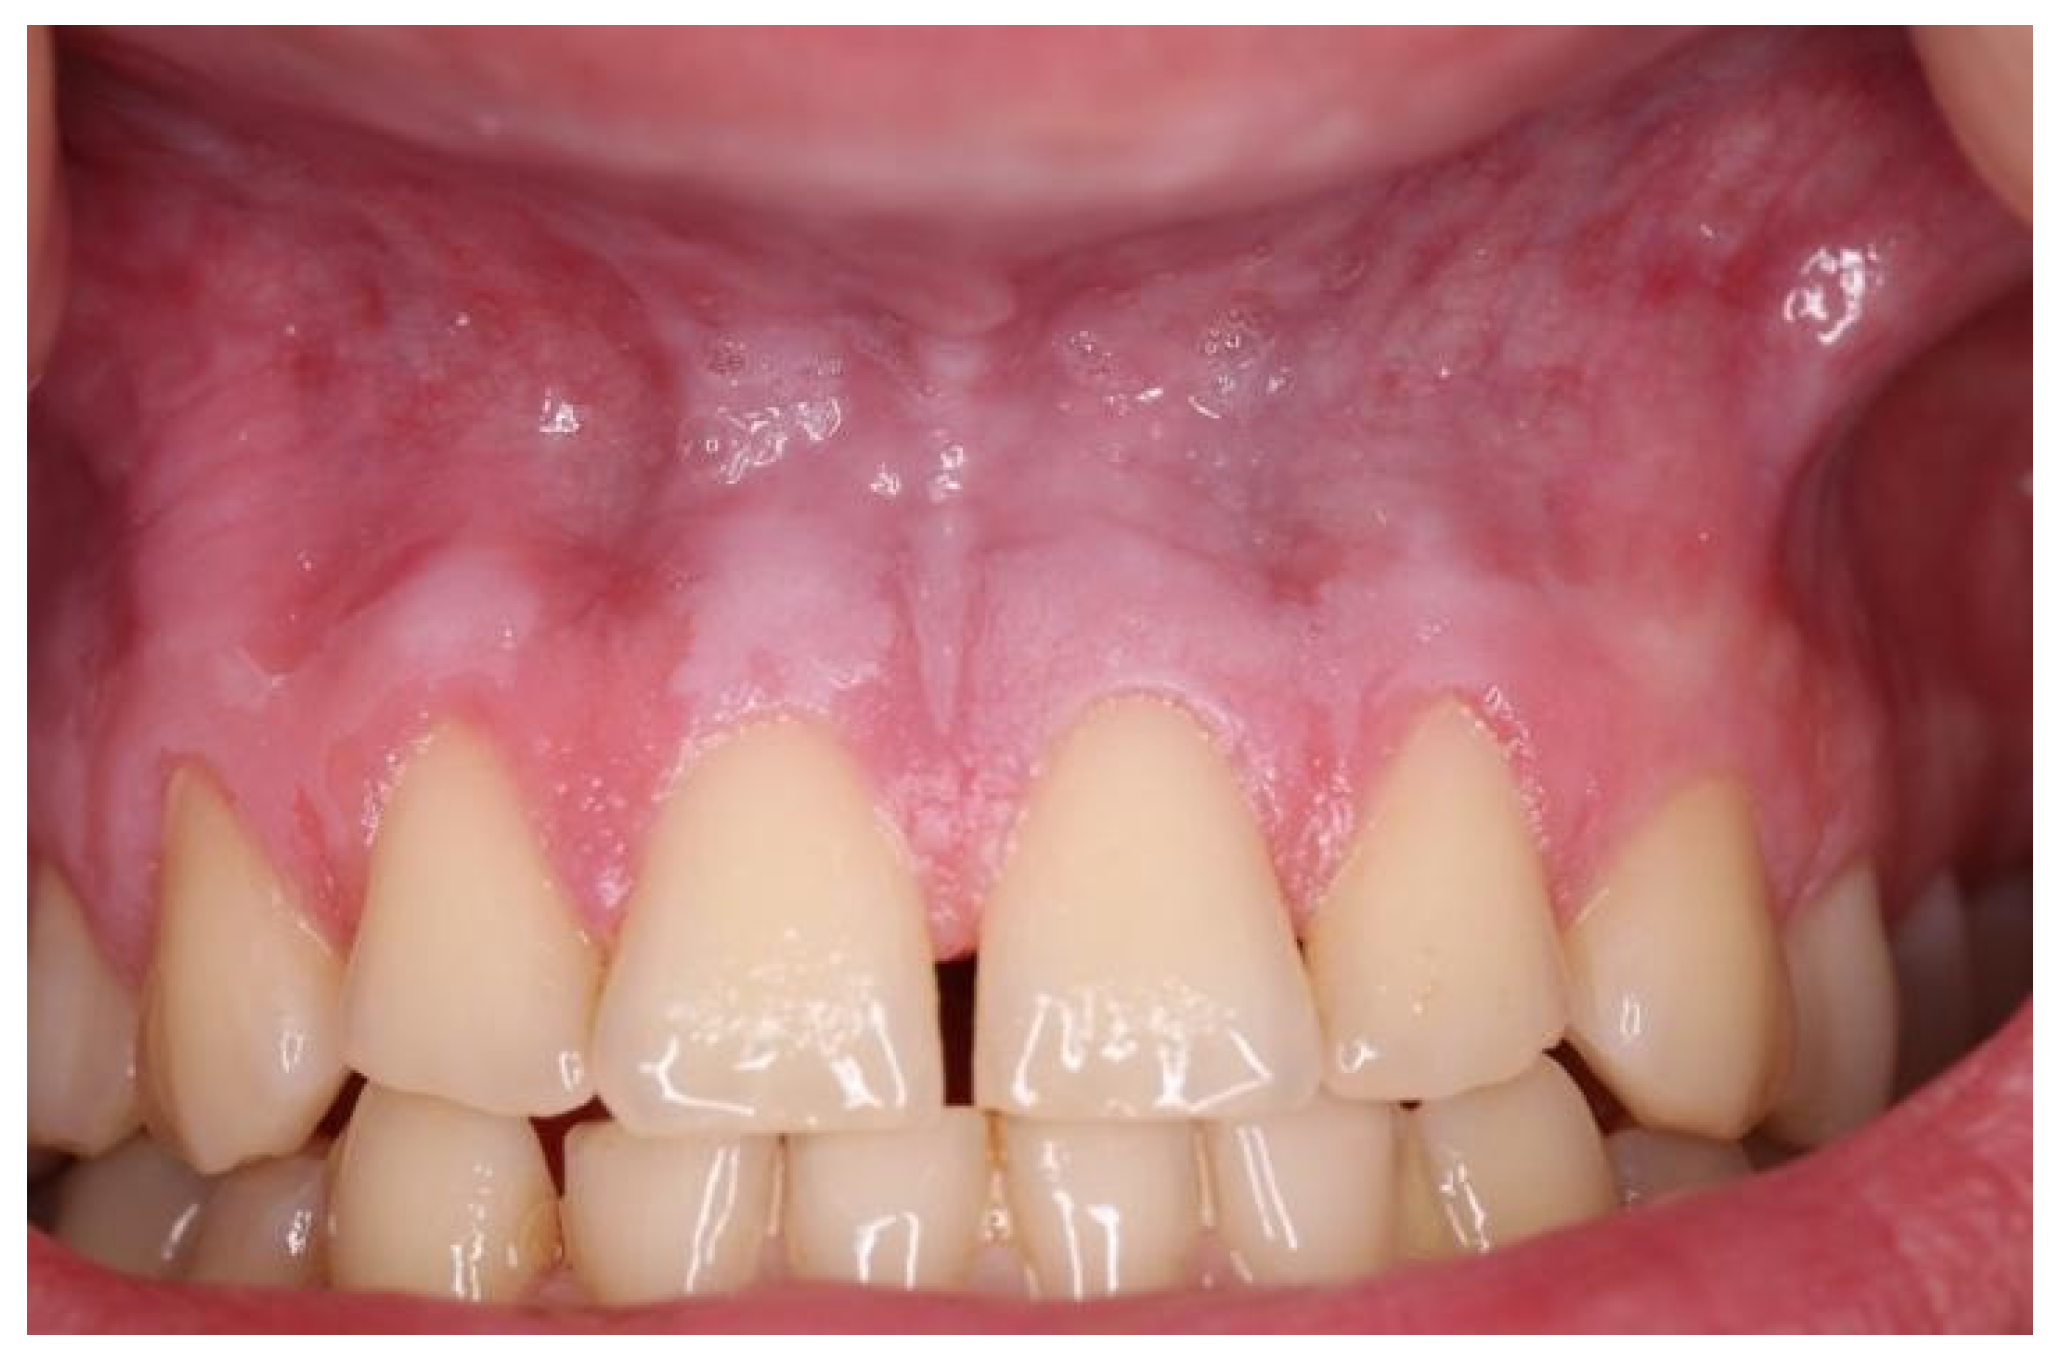

| Snus | 5–10 | 2–5 | White, leathery lesion (Figure 1) | Above tooth nr. 13 to tooth nr. 22 |